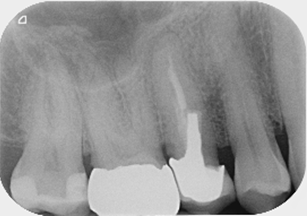

Pre-operative

Post-operative